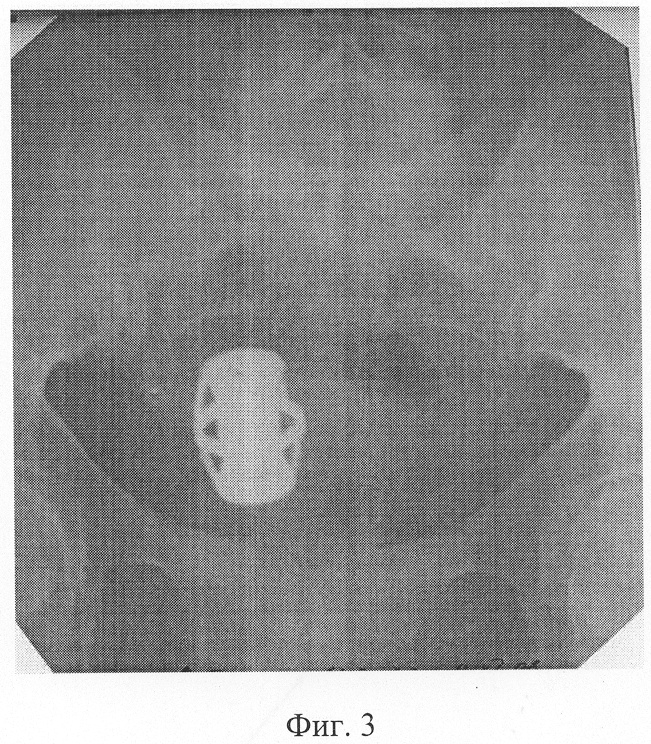

фиг.4 – ирригограмма больной П. на 14 сутки после операции, отсутствие рефлюкса контраста в тонкую кишку;

Компрессионное устройство отошло на 10 сутки после операции (фиг.4).